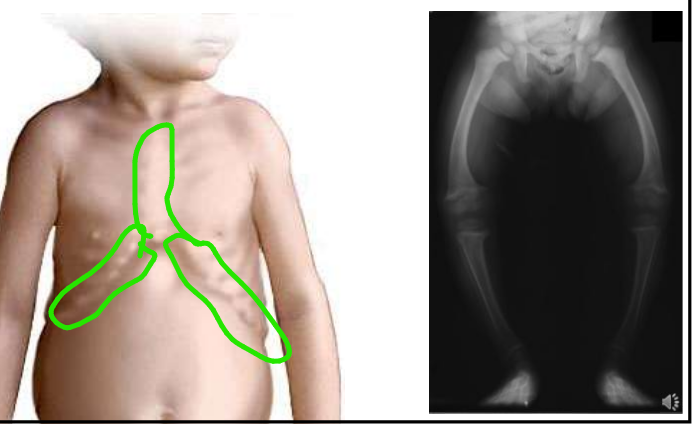

dėl ko gali būti Ca druskų deficitas audiniuose

vit. D stokos ir sutrikusios Ca rezorbcijos

kokias ligas lemia Ca druskų deficitas

rachitas - vaikams

osteomaliacija - suaugusiems

rachito morfologija

plačios epifizinės linijos - rachitiniai karoliai

subperiostinės medž. perteklius kaktikaulyje ir maleoluose (kulnkšneliusoe) -deformuoti kaulai

pakaušio kaulo lankstumas

kojų iškrypimas X, O

kaulinės sijos netvarkingos

osteomaliacijos požymiai

minkšti kaulai

lengvi lūžiai